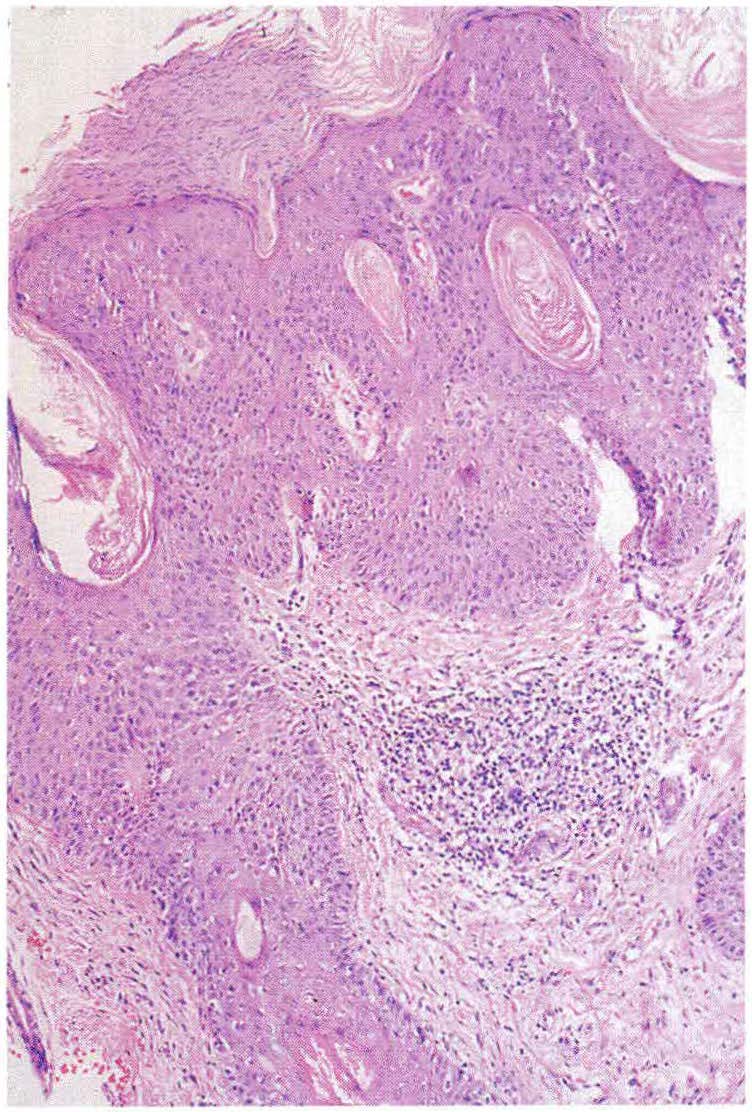

Carcinoma de células escamosas cutáneo - Parte II Histopatología y tratamiento basado en factores de riesgo

El objetivo del presente artículo es estudiar la histopatología del CEC para posteriormente analizar los factores, tanto clínicos como histológicos, que influyen en su pronóstico. Con las herramientas anteriores se hará una revisión de las diferentes modalidades terapéuticas para el manejo de CEC. Este enfoque terapéutico se basará en los factores de riesgo estudiados.